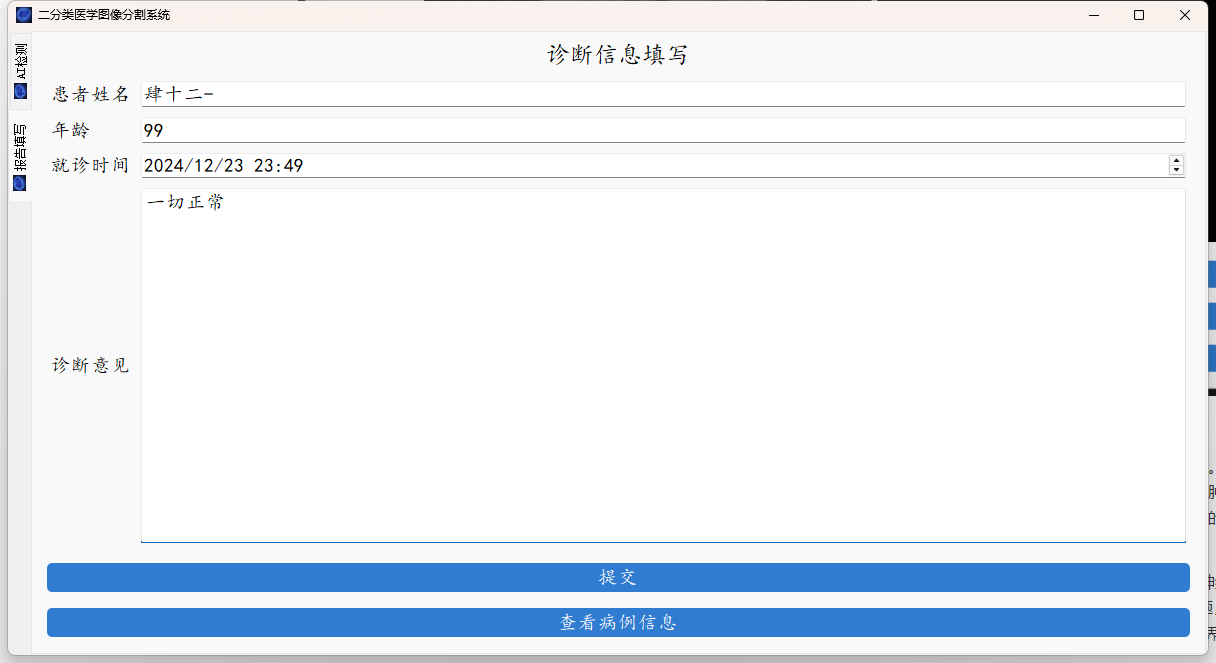

图形化界面封装

最后就是图形化界面的封装了,这里我们使用了pyqt的技术。

系统支持医学图像的分割、轮廓的查找以及简单的病例的记录。